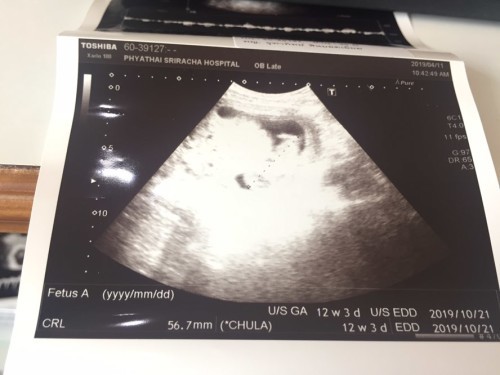

12 วีคค่ะ หมอตรวจเลือดด้วยค่ะ รอบนี้เอามือปิดหน้าไม่ให้ใครมองเลยสงสัยจำรำคานคุณหมอใช้เครื่องซาวเคาะท้องมากไป เพื่อตรวจดูน้ำที่ช่วงคอของลูกค่ะ เสียดายมากไม่ได้เห็นหน้า รอบต่อไปนัดดูเพศลูกแล้วค่ะ ตื่นเต้นมาก

เพิ่งซาวด์เมื่อวานค่ะ (18/03/62) 12w3d 😊

บ้านนี้ ซาวด์ตอน 12w จ้า แต่ในใบซาวด์ 11w